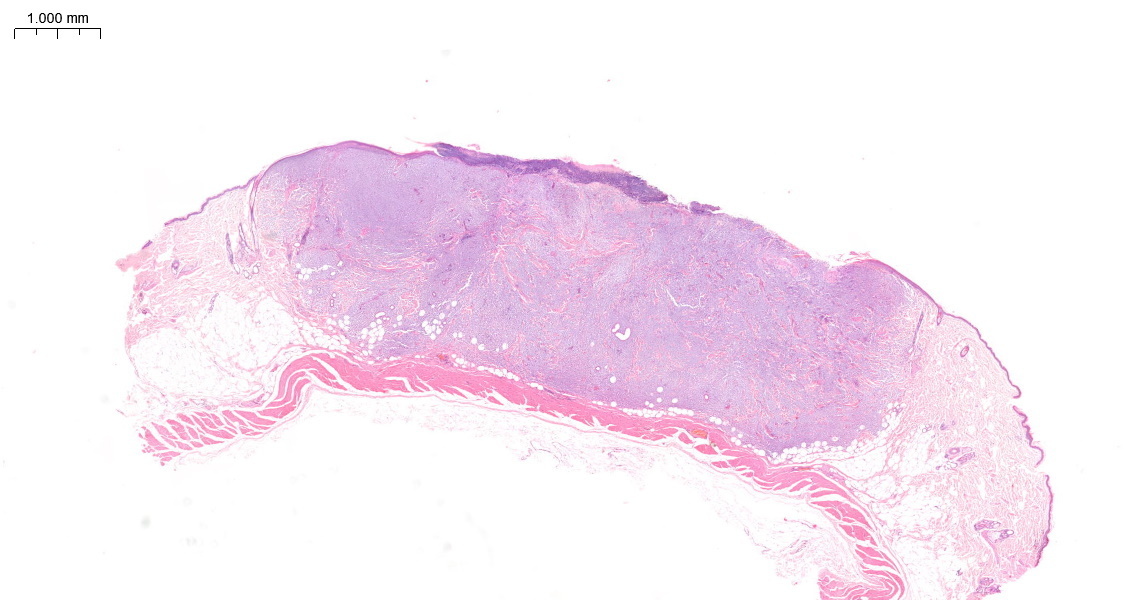

One particular case concerned a six-year-old male ferret. The lesion was a 10mm diameter raised ulcerated mass from the dorsum (Figure 1).